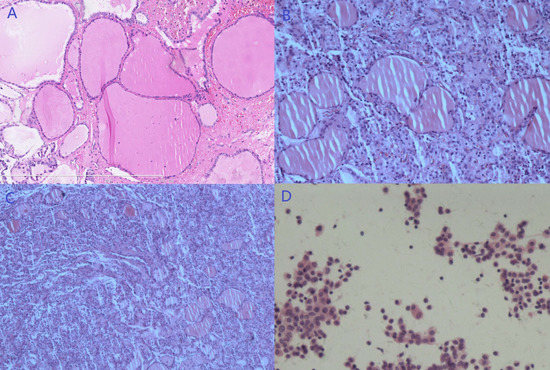

3.1.1. Case 1

3.1.2. Case 2

3.1.3. Case 3